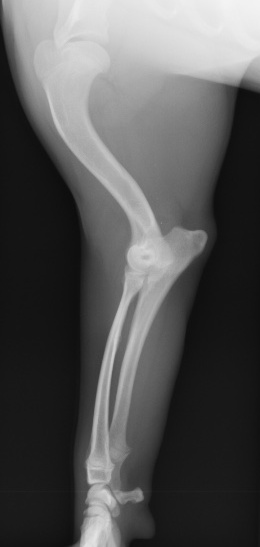

術後2か月程度で骨癒合が確認されたため、スクリューとピンの予定となりました。

その後数週間で抜いたスクリューとピンの部位の骨増生を認めたため、定期的なX線検査により経過を観察して治療終了としました。